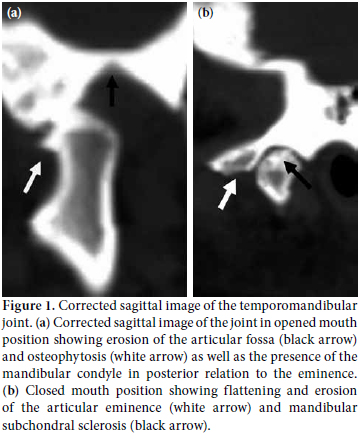

The TMJ clinical and corrected sagittal MSCT findings are shown in Table 2. Symptomatic TMJ involvement was present in 17 of the RA patients while the TMJ osseous involvement detected by MPR MSCT scan became more frequent (83.33%) as it involved three additional asymptomatic cases. The radiographic findings of the TMJ are presented in Figure 1. The mean CT TMJ score of all the RA patients was 4±3.93. There was no significant difference between the constructed coronal and corrected sagittal MSCT findings except for a higher frequency of detection of mandibular condylar shape alteration by the coronal plane (p=0.043).

In the present study, symptomatic TMJ involvement was present in 70.83% of the RA patients. The joints were bilaterally involved in all patients; however, in a small number of cases, some clinical features such as tenderness, clicking, and locking were unilateral. The most frequent clinical TMJ dysfunction manifestations were difficult manipulation and pain, tenderness (45.83%), clicking (29.17%), and locking (16.67%) followed by altered mouth opening (8.33%). The TMJ osseous involvement became more frequent (83.33%), and bilateral usage of the MPR MSCT scans in the RA patients increased with the three additional asymptomatic cases (12.5%). The most frequent findings were mandibular condyle erosions (62.5%), altered condyle position (54.17%), mandibular subchondral sclerosis (41.67%), articular eminence flattening (41.67%), altered condyle shape and articular fossa erosion (37.5%), osteophytes (33.33%), articular eminence erosion (25%), and mandibular subcondral cysts (20.83%). The MIO was reduced <30 mm in 41.67% of the patients.